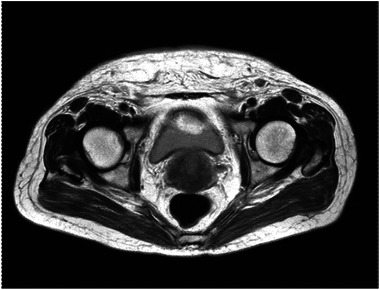

Cervical cancer, the fourth most common cancer among females in the world, ranks the second in China. In advanced disease, metastases may be commonly present in the lungs, bones, liver and lymph nodes or elsewhere, but uncommon to the skin. In this report, a 63-year-old woman was diagnosed as stage IVB cervical squamous cell cancer in January 2021. The patient was scheduled for concurrent chemoradiotherapy; however, a metastatic lesion of skin was proved by biopsy during the process of treatment. She died 1 month after confirmed skin metastases. Cutaneous metastasis of cervical cancer may predict the mix of lymphatic and hematogenous metastasis and the rapid fatal termination.